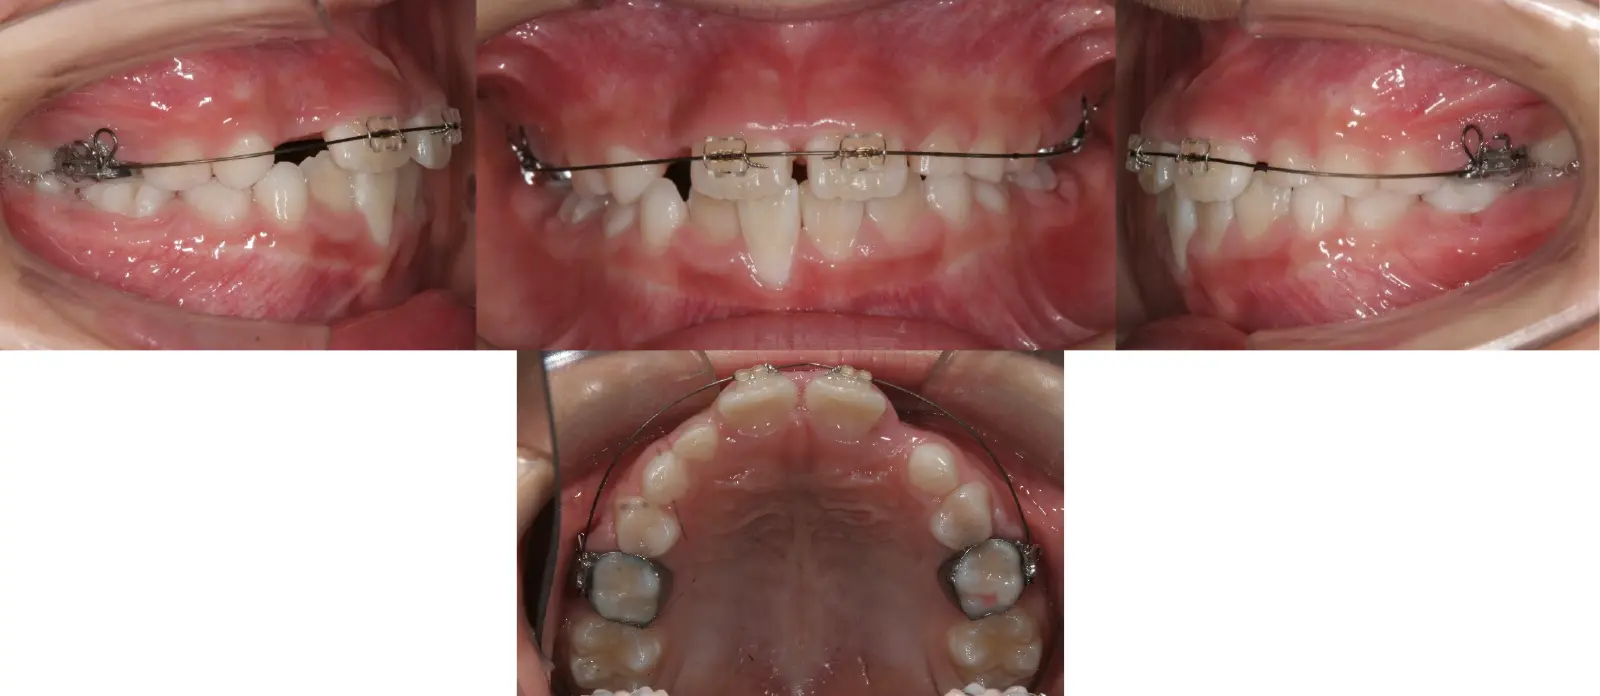

1歯のみの反対咬合

第一段階の治療のみで、

永久歯は問題なく萌出し、安定している

- 主訴

1歯のみの逆破蓋

- 年齢

8歳

- 治療期間

7ヶ月

- 治療回数

5回

- 治療に用いた主な装置

拡大床

- 治療費

400,000円(税別)トータル料金